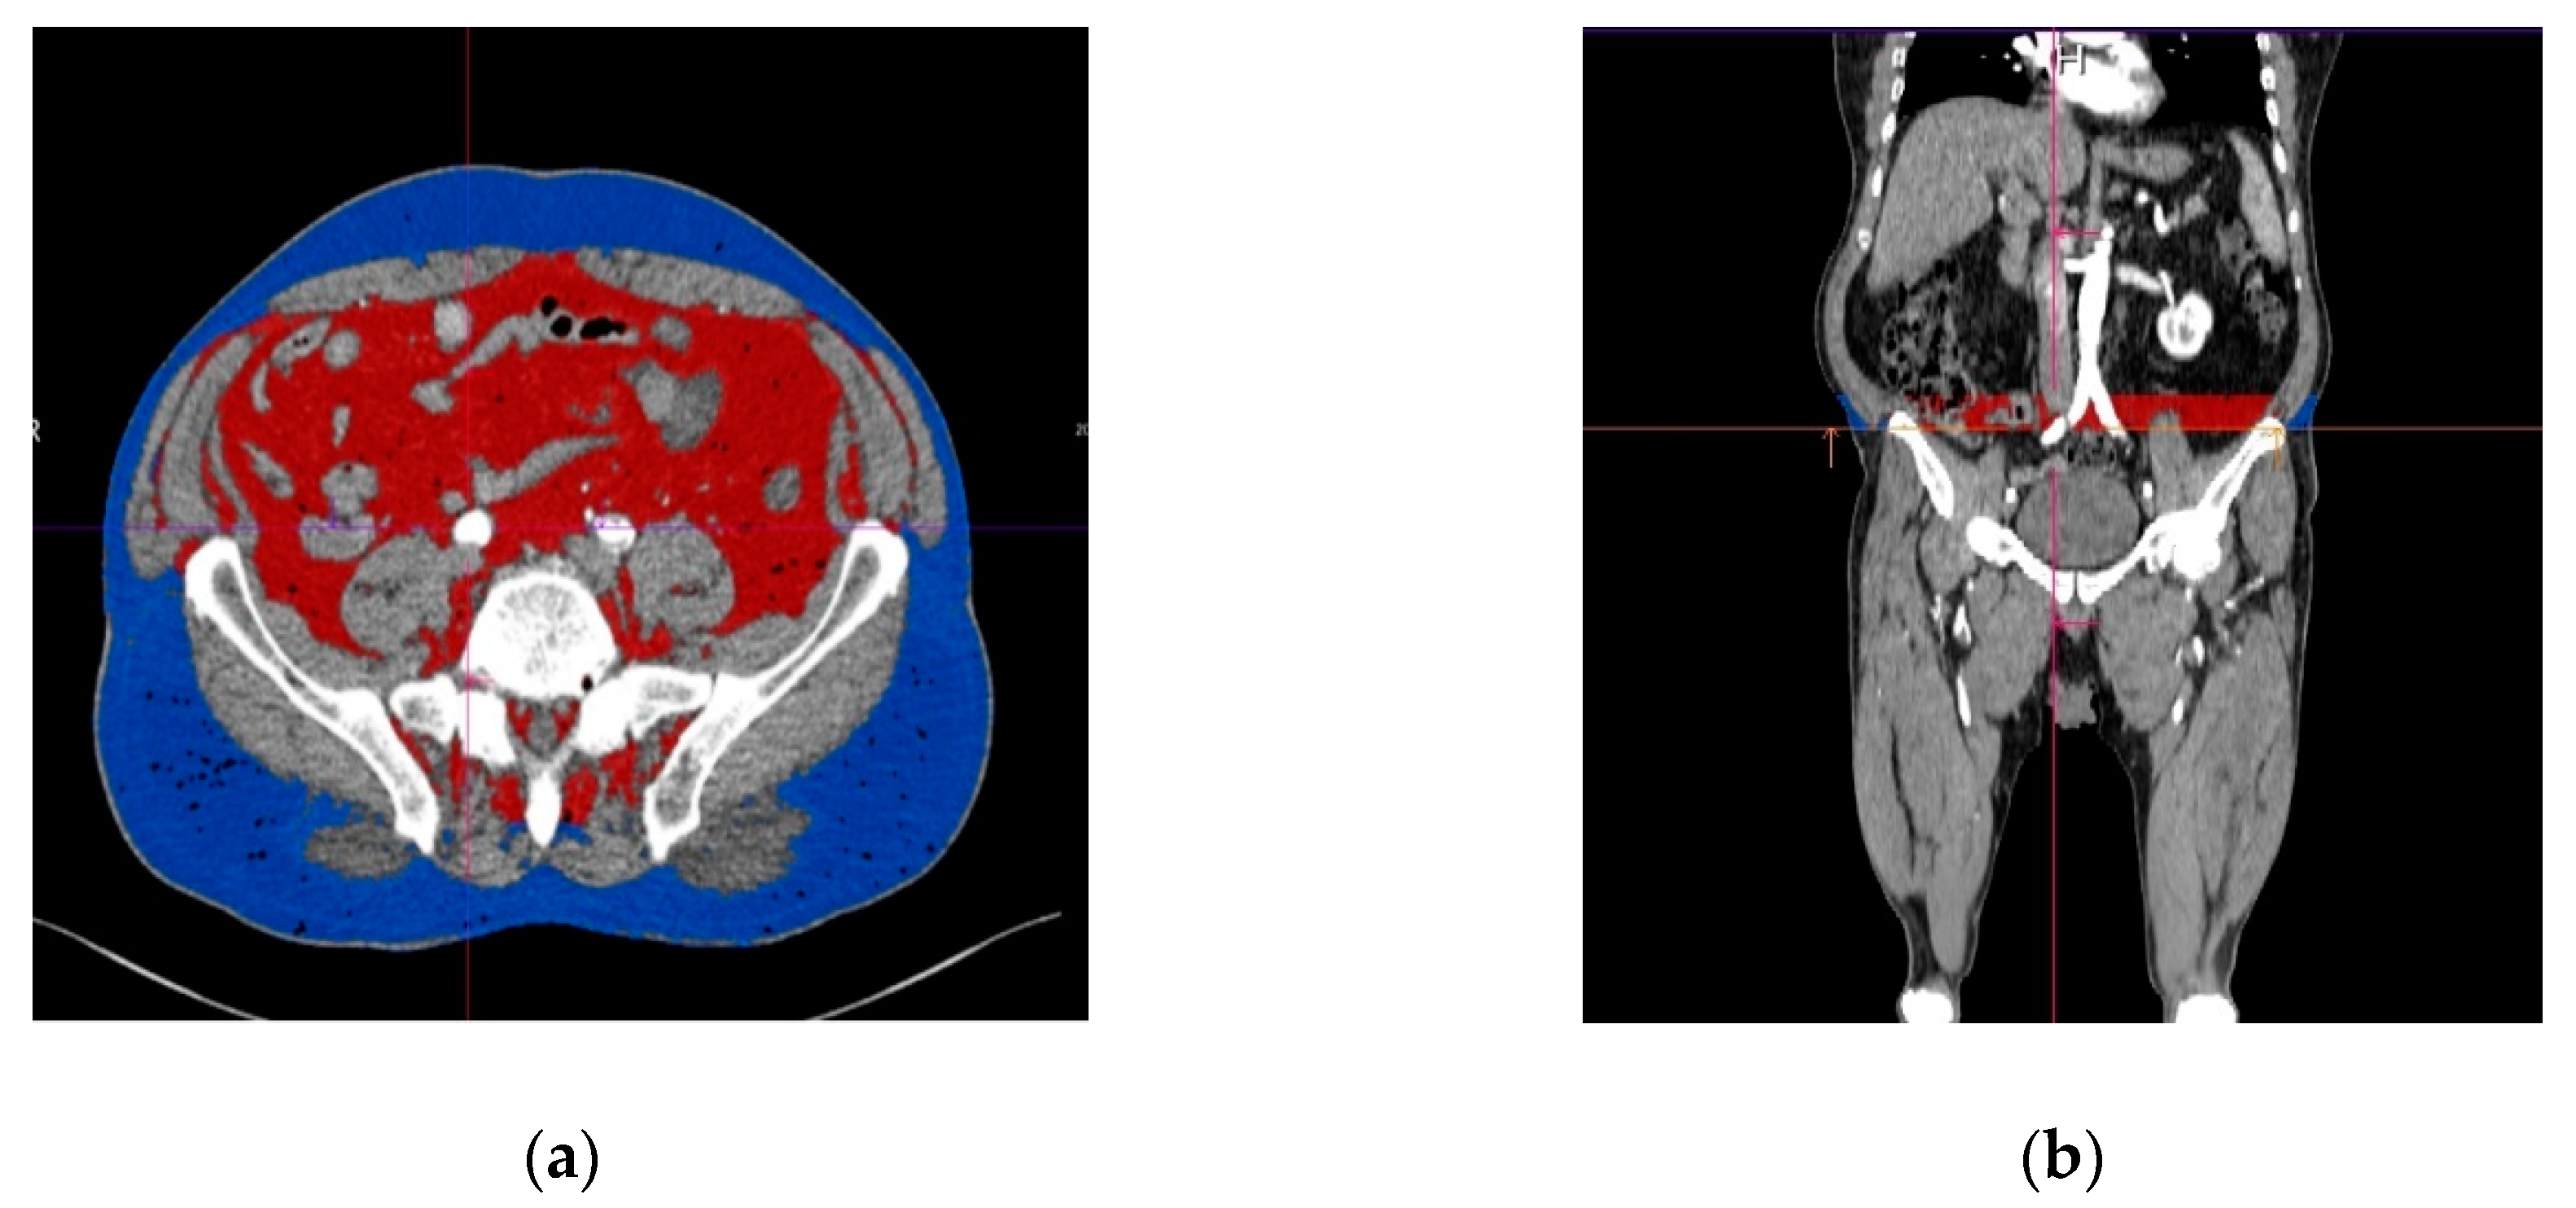

The volume of the PIAT was measured for both the right and left common iliac arteries, along the whole vessel and on each slice. The border of the PIAT was manually traced around the vessel, throughout the whole length of the iliac arteries, at a limit of 2 cm from the vessel border. After opening the imaging acquisition with the dedicate postprocessing software, a circle was manually traced around the target common iliac artery. The traced circle was manually adjusted in order to mark the tissues correctly around the vessel, at 2 cm outwards from the vascular wall. The following step included manual delineation of the circular border of the vessel at the bifurcation of the common iliac artery. The postprocessing software allowed automatic interpolation of the contours in a longitudinal direction on the examined segments and measurement of the perivascular adipose tissue using a color-coded system for a superior representation (Figure 2a,b). The software automatically detects the volume of the periiliac adipose tissue (with a CT attenuation ranging between −150 to −50 HU) after interpolation of contours, with a color-coded display. The volume of the perivascular adipose tissue was automatically calculated and displayed expressed in milliliters and with red color. The subcutaneous and visceral adipose tissue are represented with blue color.

Figure 2.

Perivascular adipose tissue surrounding left common iliac artery (marked in red color). (a) Transverse section; (b) longitudinal section, with the region of interest immediately after the origin of the iliac arteries from the aorta. The subcutaneous adipose tissue is represented in blue.